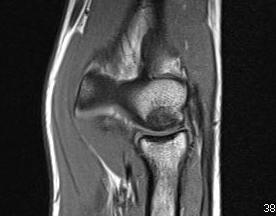

MRI

Fluid interface denotes detachment / instability

MRI Classification

Stable

- cartilage intact

- no fluid behind lesion

Unstable

- cartilage breach

- fluid behind lesion